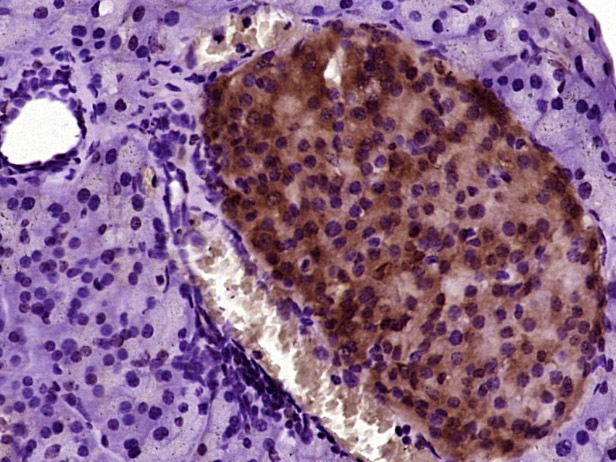

Paraformaldehyde-fixed, paraffin embedded (mouse pancreas tissue); Antigen retrieval by boiling in sodium citrate buffer (pH6.0) for 15min; Block endogenous peroxidase by 3% hydrogen peroxide for 20 minutes; Blocking buffer (normal goat serum) at 37°C for 30min; Antibody incubation with (CAPH2) Polyclonal Antibody, Unconjugated (bs-24076R) at 1:400 overnight at 4°C, followed by operating according to SP Kit(Rabbit) (sp-0023) instructionsand DAB staining